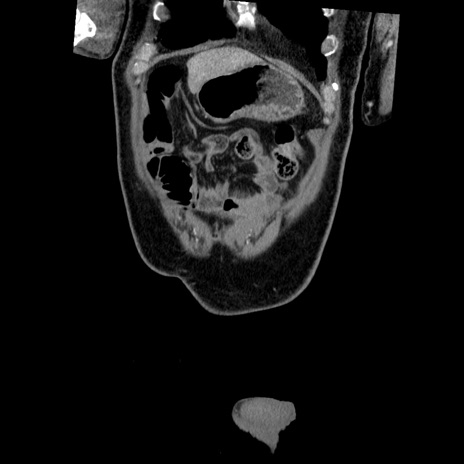

症例22(冠状断像)

【症例】50歳代男性

【主訴】腹痛

【現病歴】AVMからの被殻出血のため回復期リハ病棟入院中。 本日午後3時頃急に下腹部痛が出現した。

【既往歴】AVM、被殻出血、虫垂炎、高血圧

【身体所見】意識晴明、左半身不全麻痺、会話の理解は良好、36.5°C、腹部:膨隆、全体に板状硬、下腹部正中に圧痛点あり、反跳痛-、筋性防御不明、右下腹部にope scar

【データ】WBC 9400、CRP 0.06